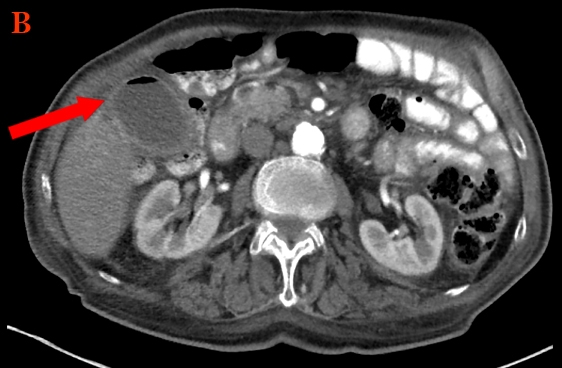

The diagnosis of colovesical fistula is established with a CT scan of the abdomen and pelvis with either oral or rectal (NOT intravenous) contrast.

In patients with colovesical fistula, this will show contrast in the bladder and localized thickening of the bladder and colon walls.

Abscesses measuring <3cm (ring enhancing fluid collection) are not amenable to be treated by CT-guided percutaneous drainage and may resolve with antibiotics alone; those measuring >3cm should undergo CT-guided percutaneous drainage.

Complicated diverticulitis refers to diverticulitis associated with an abscess (as seen in this patient), perforation, obstruction, or fistula formation. A fluid collection less than 3 cm can be treated with intravenous antibiotics and observation, with surgery reserved for patients with worsening symptoms. However, a fluid collection >3 cm should have CT-guided percutaneous drainage. If the symptoms are not controlled by the fifth day, surgical drainage and debridement are recommended. Sigmoid resection is generally reserved for patients with fistulas, perforation with peritonitis, obstruction, or recurrent attacks of diverticulitis.